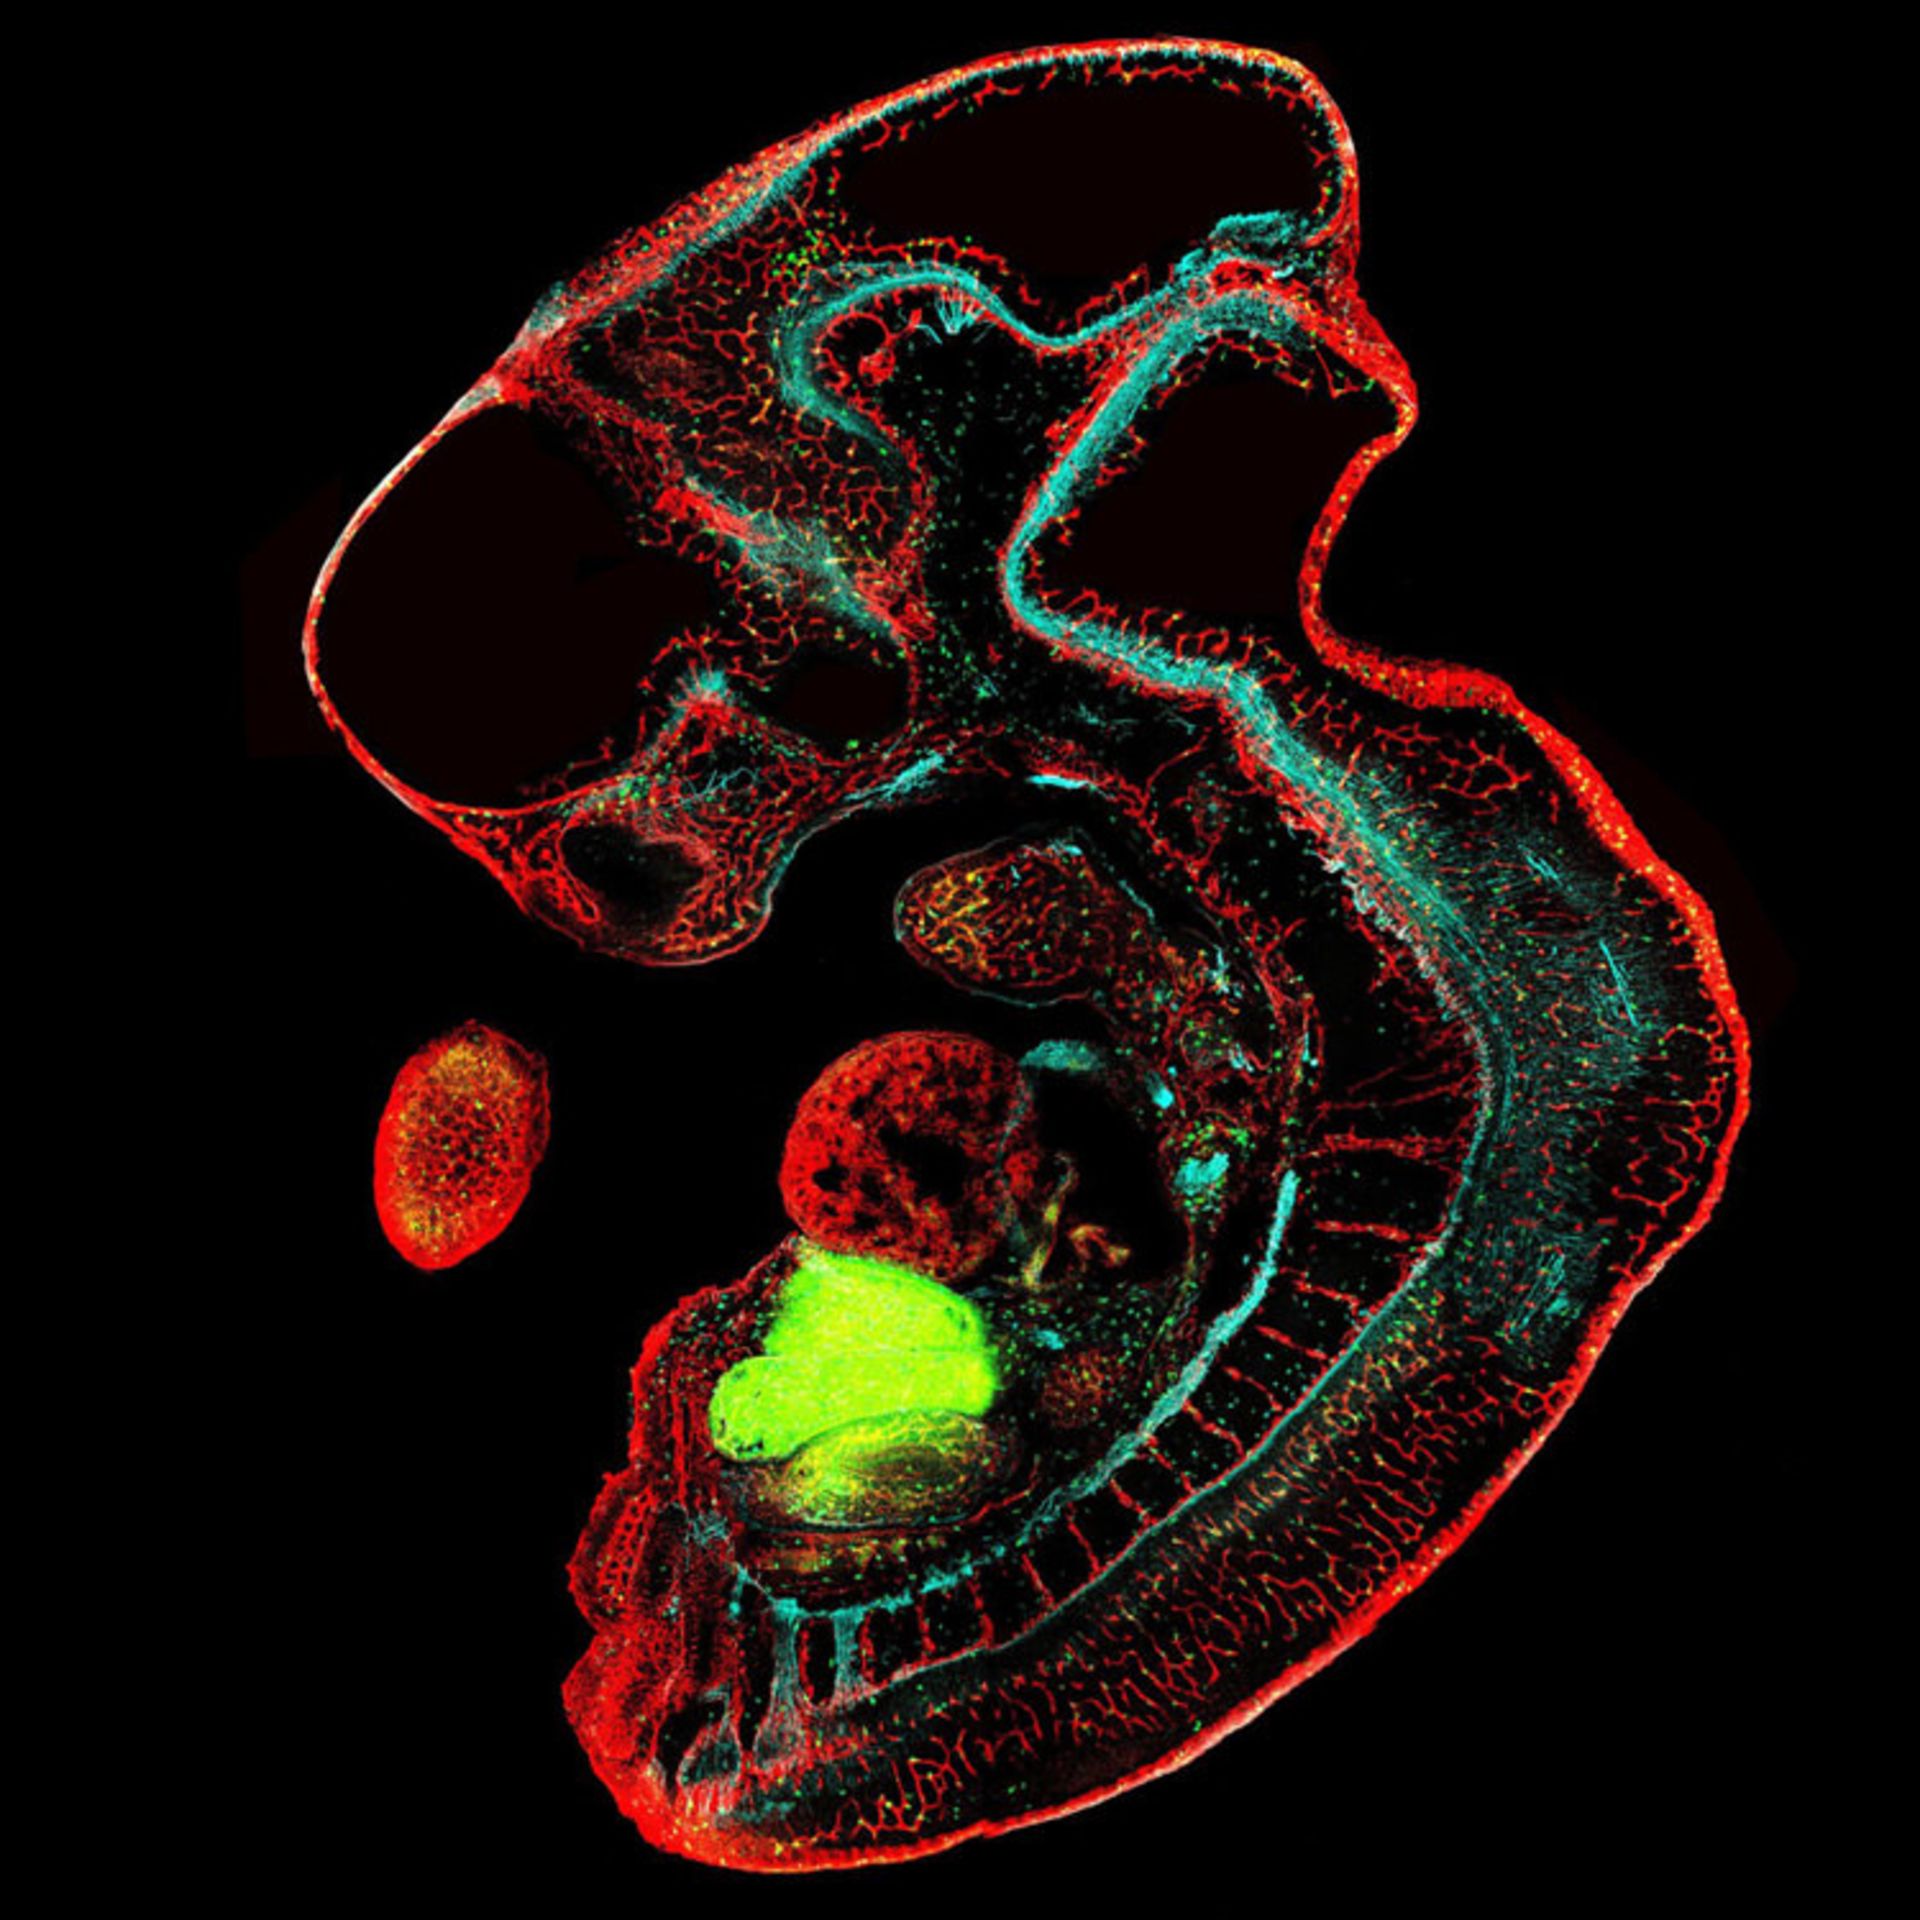

رگهای خونی (قرمز) ، اعصاب (آبی) و سلولهای ایمنی (سبز) در جنین ۱۱.۵ روزه ی موش؛ بزرگنمایی ۱۰ برابری

دکتر یان کریوانک (Dr. Jan Krivanek) از جمهوری چک